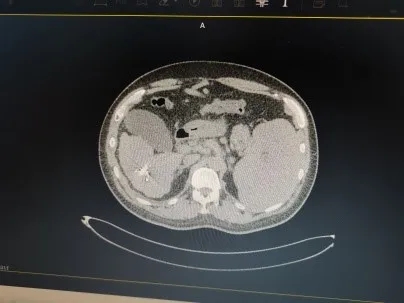

放射治疗分传统的外照射和组织间照射。传统的外照射因放射野大、正常组织耐受量低,其疗效常受到一定的限制。永久粒子植入是通过术中模板,在CT或B超引导下将放射性粒子植入肿瘤内,通过放射性粒子持续释放射线对肿瘤进行杀伤,目前临床常用的永久性植入治疗的粒子为Au、I和Pd,其中I应用最广。放射性粒子植入属于组织间内照射或微创介入性放射治疗,是近几年开展起来的治疗恶性肿瘤的新手段,主要是应用放射性粒子治疗计划系统(TPS)设计治疗方案,在CT或B超引导下将放射性粒子按肿瘤大小、形态植入肿瘤内或受肿瘤侵犯的组织中,通过放射性粒子发出持续、短距离的放射线,使肿瘤组织遭受最大程度的杀伤,而正常组织不受损伤或仅有微小损伤,最终达到治疗目的。作为传统外照射放疗及化疗的一种补充治疗手段,I放射性粒子植入治疗恶性肿瘤具有近期疗效好,副作用小,安全性高的特点。

放射性粒子植入治疗的全称是“放射性粒子组织间插植术”,属于近距离放射治疗(brachytherapy)的范畴,是通过微创方式将多个封装好的具有一定规格、活度的放射源,经施源器或施源导管用多种植入方式直接植入到肿瘤组织内部对肿瘤进行照射,达到治疗目的。

核医学医师依据事先制定的治疗计划,在CT或B超引导下,将长约4毫米、直径0.8毫米的放射性粒子准确植入肿瘤靶区,放射性粒子在体内持续不断发出射线,可使肿瘤接受的剂量明显增加,达到高剂量靶区适形治疗,由于是持续性低剂量率的照射,能够对进入不同分裂周期的肿瘤细胞进行不间断的照射,增加了放射生物效应,提高了放疗疗效。肿瘤组织间植入放射性粒子所产生的射线能量虽然不大,但能持续对肿瘤细胞起作用,不间断的杀伤肿瘤干细胞,经过足够的剂量和半衰期,即可使肿瘤细胞全部失去增殖能力,而达到彻底根除的治疗效果。由于放射性粒子源发射的射线的穿透距离短,有效射程为1.7cm,因此不会损伤到周围正常组织,更不会引起全身症状,在最大限度地杀灭肿瘤细胞的同时,减少对周围正常组织的损伤。